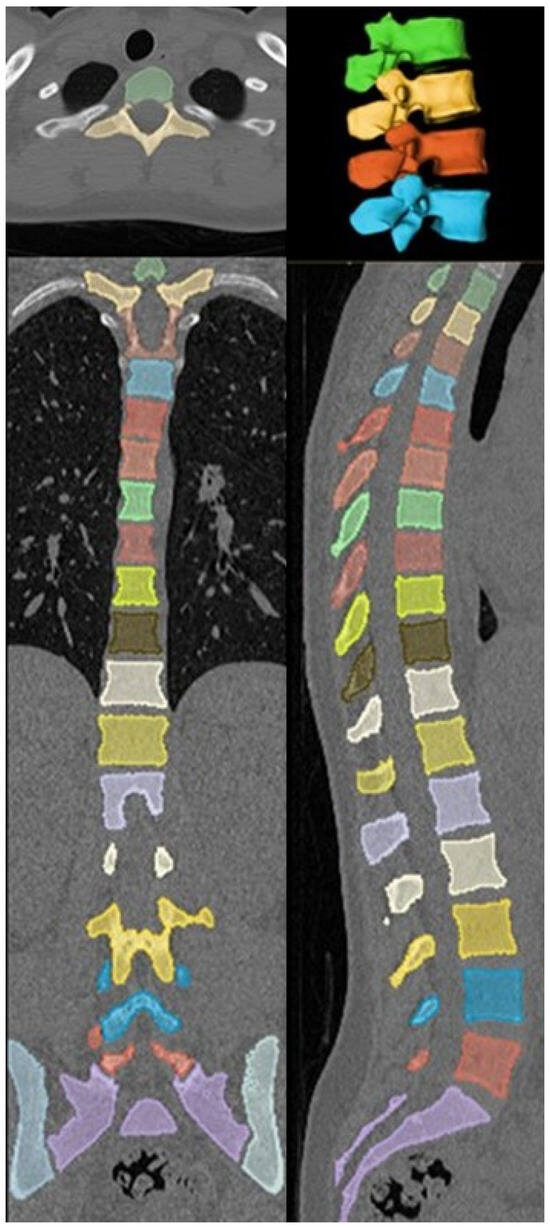

A recently developed deep-reasoning and learning-based model (DR-AI; Deep Reasoning AI Inc., Ithaca, NY, USA) was employed to automate vertebral segmentation and volumetric HU quantification of the cancellous part of the vertebrae, excluding the cortical parts and all possible osteophytes, which may lead to false-negative diagnosis. The model was developed based on publicly available data (deepreasoning3d.com) as well as deidentified patients’ data from our institution. This was performed by an imaging technologist and a research coordinator according to HIPAA guidelines [15]. It integrated deep learning for pattern recognition with reasoning capabilities to solve complex segmentation tasks in an unsupervised or weakly supervised manner [16]. Leveraging an open-source framework for the automated vertebral segmentation [11], it was trained on a dataset of CT scans with annotated vertebral labels (Figure 1). To evaluate the reliability of the automated volumetric HU measurements, random spot checks were performed on a mid-sagittal slice of the CT series using clinical image viewer software (QReads 5.15.3).

The model processed CT scans in the soft-tissue window/kernel to segment each vertebra (L1–L4) and compute volumetric HU values. The segmentation process involved identifying vertebral boundaries and excluding non-bony structures (e.g., cortical bone edges, spinal canal). Volumetric HU was automatically calculated as the mean HU across all voxels within the segmented vertebral body excluding the cortical bone.

A total of 84 patients (67 females and 17 males) met the inclusion and exclusion criteria. All patients were Caucasian, and mean age at imaging was 74.1 ± 10.3 years for females and 68.1 ± 12.4 years for males. The deep-reasoning and learning-based model (DR-AI) successfully demonstrated robust performance in segmenting and quantifying volumetric HU for all L1–L4 vertebrae with high fidelity. Random spot checks confirmed accurate delineation of vertebral boundaries, with no significant discrepancies between automated and manual measurements on mid-sagittal slices (Figure 2). The model processed each CT scan in approximately 30.4 s when hosted on an A100 NVIDIA GPU, (NVIDIA Corp., Santa Clara, CA, USA) providing both the volumetric HU and volume for all scanned vertebrae from all available kernels (Figure 3).

Figure 3. Automated vertebral segmentation generated from the DR-AI model.